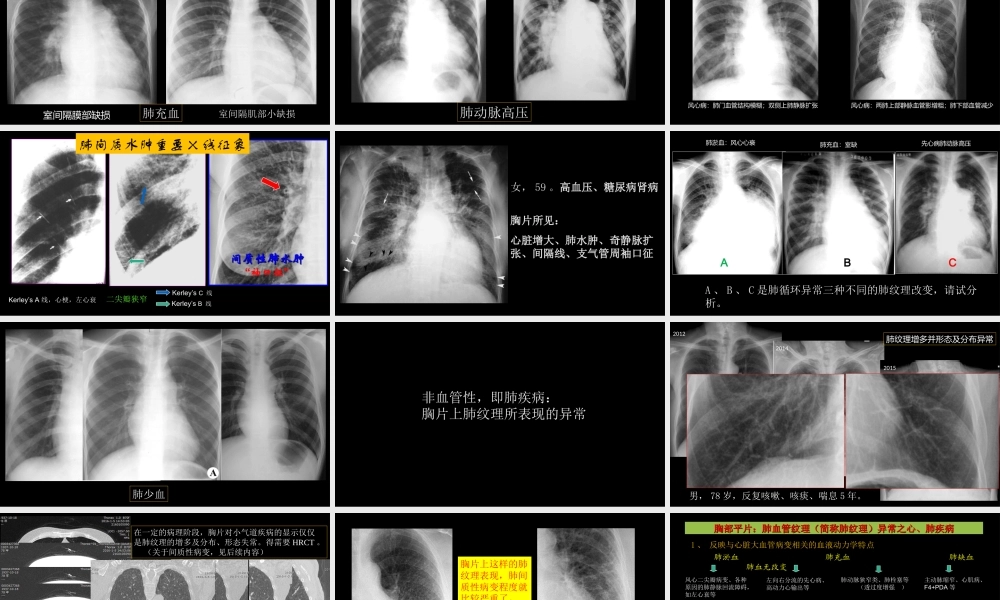

肺血管及肺网状结构的影像学与心肺疾病杨景震中国石油中心医院影像科(注:内有动画设置,请选择幻灯片放映模式浏览)主要内容•胸片上肺纹理的概念与相关病理意义•肺纹理(心血管源性、非血管源性)与X线胸片•肺血管的CT表现•肺网状结构与HRCT•心、肺影像学病例——大家解读胸片之肺纹理的概念与相关病理意义肺纹理的定义在正常X线胸片上,从肺门向肺野外围延伸的放射状条状阴影。其组成主要是肺动脉的影像,其次为肺静脉、支气管和淋巴管参与并形成这种特有的X线表现。肺纹理是传统X线技术用于描述肺部影像的专用术语。CT图像中不使用该词。肺纹理成像的条件:肺组织处于良好的充气状态。当肺部存在病变时,而肺部充气不良,肺纹理不得充分显示。肺纹理X线胸片的意义:1、胸片上肺纹理异常,比如肺纹理增强只是一个X线征象,需要具体分析其他特征或临床资料,才有实际意义。2、心肺一体的疾病,心肺存在相互病理关系,因此,X线胸片具有很重要应用价值。3、避免误区:肺纹理增强,均判支气管炎;正常情况下,肺纹理CR或DR片较传统X片多、右下较对侧多、老年人较年轻者多。CT检查:1、不采用“肺纹理”一词,因平片上的肺纹理属于多结构的混合影像,而于CT上更具体,没有重叠,显示直观。2、直接描述“肺血管”,薄层图像显示垂直层面的肺血管呈点状。叶间裂区稀疏。3、CT可区分肺间质的病变(表现为网状结构)、肺血管的异常。4、增强扫描可以显示肺栓塞5、心肺一体的病变应参考胸片分析,例如,左心功能不全与肺水肿MRI检查:高档设备只是对于肺血管作评价,对肺间质的网状结构不及HRCT。胸片上出现肺纹理的异常:数量的异常;形态的异常数量的异常:增多;减少;缺失形态的异常:增粗、纤细;走行异常、分布异常(稀疏或聚拢)肺纹理增多:见于血管性、支气管性、淋巴管性、肺间质性血管源性:肺动脉:纹理粗大,边界清楚、主枝近乎于纵向分布,肺门动脉扩张,心影异常。比如左向右分流的先心病肺静脉:纹理增粗以双侧上肺内侧为著,肺野表现为增多的肺纹理边界模糊,比如风心病二尖瓣狭窄,各种左心功能不全。支气管源性:增多,粗细不均,夹杂变形纹理和小蜂窝影像,有时可见轨道征,双下明显,如慢支、支扩。淋巴管源与肺间质性:增多表现为肺内纤细而增多的网状,如尘肺,癌性淋巴管炎、肺纤维化组疾病等。其他方面:急性发热;肺小动脉硬化等。肺纹理数量减少或缺失肺纹理减少:气道的原因——肺气肿;小气道阻塞性疾...